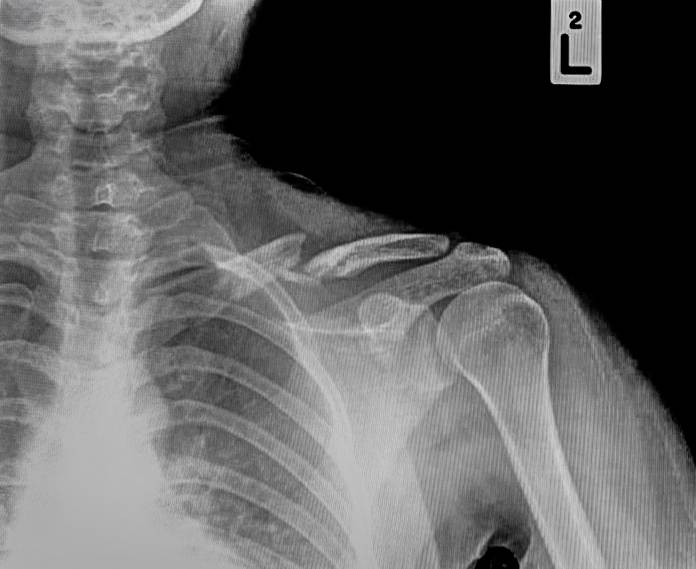

Auf dem Röntgenbild ist der Knochenbruch meist gut zu sehen. Im Zweifelsfall kann eine Computertomographie (CT) angefertigt werden. Eine Kernspintomographie (MRT, Magnetresonanztomographie) kann aufdecken, ob sich weitere Schäden an Gelenken oder Bändern ergeben haben.